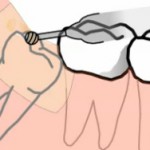

Зубной цемент – очень важный материал в стоматологической практике. Он используется в основном для фиксации искусственных коронок. Иногда, установленная ранее коронка по каким-либо причинам распломбировывается, и если под коронкой зуб не повреждён, коронку можно поставить на место, приклеив её. Для фиксации материал можно купить в аптеке, для этого нужно знать, сколько стоит зубной цемент.

Когда может возникнуть распломбировка коронок

Распломбировка коронок может возникнуть в следующих клинических ситуациях:

1. При развитии кариозного процесса. Чтобы предотвратить развитие кариеса нужно регулярно чистить зубы, используя при этом не только зубную пасту и щётку, но и зубную нить и ополаскиватель для ротовой полости.

2. Тянущие пищевые продукты, такие как ириски.

3. Дефект в искусственной коронке. В этот дефект постоянно поступает жидкость, в том числе и слюна, что заканчивается распломбировкой.

4. Такие вредные привычки, как скрежет зубами, привычка грызть ногти или какие-либо предметы.